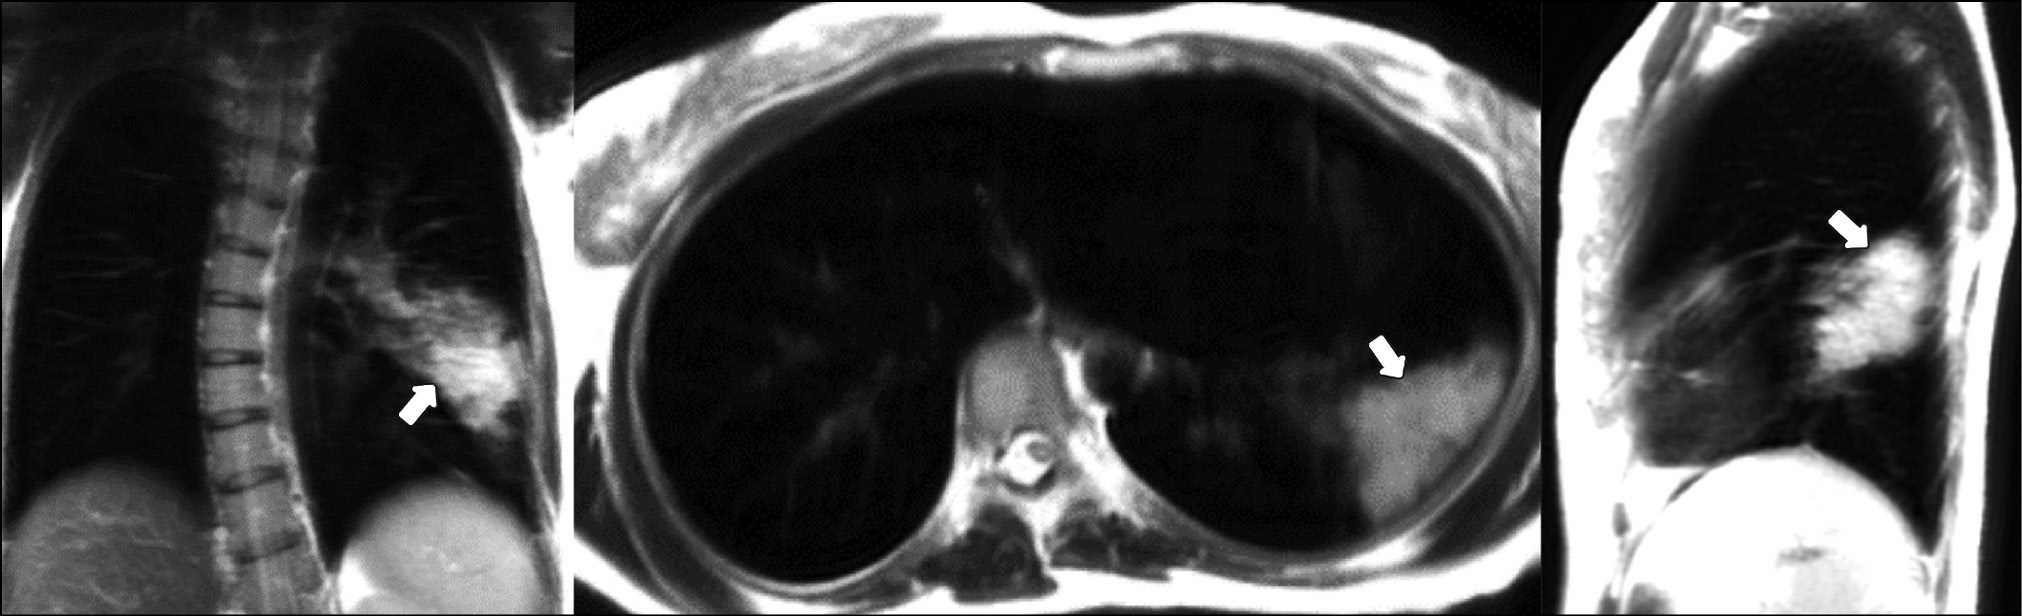

A patient (female, 45 years old) presented to the clinic on the fifth day after the onset of dry cough and mild fever up to 37.5°С. Dynamic lung MRI in the coronal plane (Fig. 1) showed an area of hyperintense signal in the lower lobe of the right lung (S9–S10), interpreted as an area of central induration (more intense signal) with a surrounding “cloudy sky” (less intense signal) during inhalation. A hyperintense signal was found in the corresponding area in the axial and sagittal planes, indicating consolidation with a “cloudy sky” along the edge of the area. At the end of exhalation, increased signal intensity was observed in the described area in the coronal plane (Fig. 2) with decreased visual size of the affected areas due to lung tissue contraction. During exhalation, no changes in signal intensity were observed in the axial and sagittal planes.

Figure 2. Dynamic magnetic resonance imaging of the lungs during exhalation in the coronal, axial, and sagittal planes. Arrows indicate the areas of consolidation (S9–S10).

If the same hyperintense signal is observed regardless of respiration phases, this could indicate alveolar infiltration (consolidation), but a less intense signal during exhalation could indicate intermediate changes (cloudy sky”).